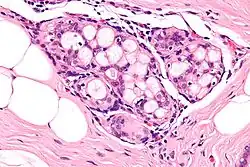

Collagenous spherulosis is characterized by a tubular/cribriform architecture with intratubular eosinophilic material that classically is arranged like the spokes of a wheel ("radial spikes"). There is usually no mitotic activity, and two cells populations (epithelial & myoepithelial) are present, like in benign breast glands.

The lesions are typically small (less than 50 spherules per lesion, less than 100 micrometers in size) and may be multifocal.